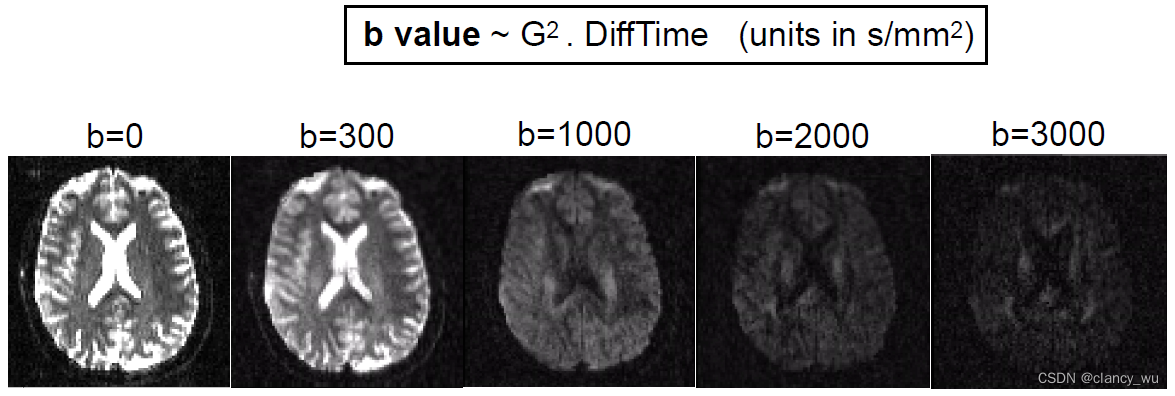

场强大小,其实就是我们研究DTI像经常会看到的变量,即B值,B0,B1000,B3000等。